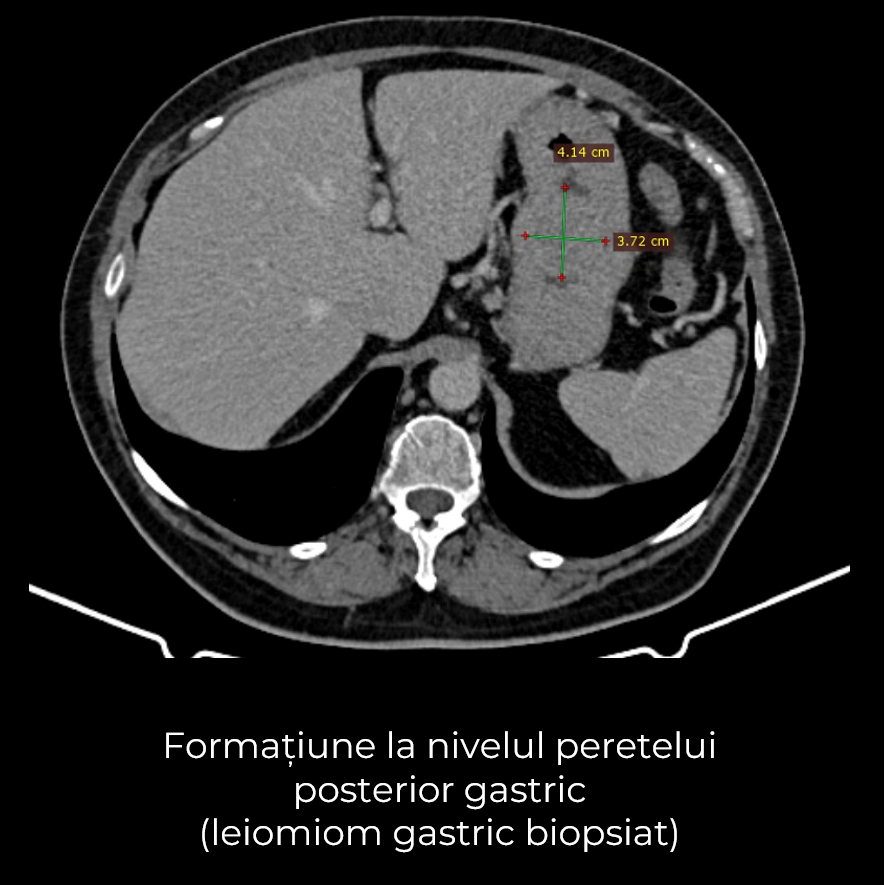

Uneori, o durere aparent banală ascunde în spate o realitate medicală mult mai serioasă. Așa s-a întâmplat și în cazul unei paciente de 63 de ani, care a ajuns la spital pentru dureri pelvine persistente. Investigația CT a schimbat însă complet perspectiva: au fost descoperite trei formațiuni tumorale în zone diferite ale corpului – o tumoră mamară stângă (carcinom mamar invaziv biopsiat), o tumoră pelvi-abdominală voluminoasă (tumoră ovariană) și o formațiune la nivelul peretelui posterior gastric (leiomiom gastric biopsiat).

- Gastrectomie segmentară – excizia porțiunii afectate din stomac